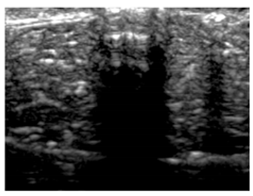

3.3. B-Mode Images

3.5. Echogenicity

4.1. Ultrasonography and Aerogel Dimensional Analyis

| Aerogel Type | US Image | Normalized Intensity Map | 3D Intensity Map | |

|---|---|---|---|---|

| 1 | Muscle |  |  |  |

| 2 | X-silica |  |  |  |

| 3 | X-silica-La2O2S:Eu |  |  |  |

| 4 | SMPU-Mix-14 |  |  |  |

| 5 | SMPU-Mix-18 |  |  |  |

| 6 | BRF-CA |  |  |  |

| 7 | ARF-CA |  |  |  |

| 8 | X-Ca-Alg-2 |  |  |  |

| 9 | X-Ca-Alg-1 |  |  |  |